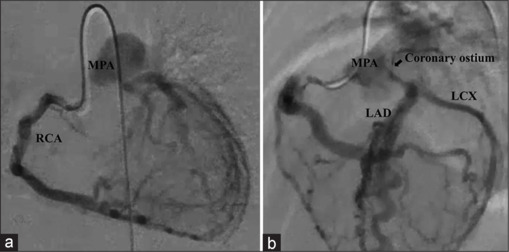

Imaging details of asymptomatic, nonischemic cases of anomalous left coronary artery from the pulmonary artery (ALCAPA) diagnosed in infancy are not well established. A 6-month-old girl was diagnosed with ALCAPA but showed normal left ventricular contraction. Echocardiography and coronary angiography revealed abundant collateral pathways from the right coronary artery to the left coronary artery (LCA), with the opening of the pulmonary artery narrowed to 1.5 mm and a restricted continuous flow from the LCA to the pulmonary artery. Coronary ostial stenosis could be one of the findings in asymptomatic, nonischemic ALCAPA.